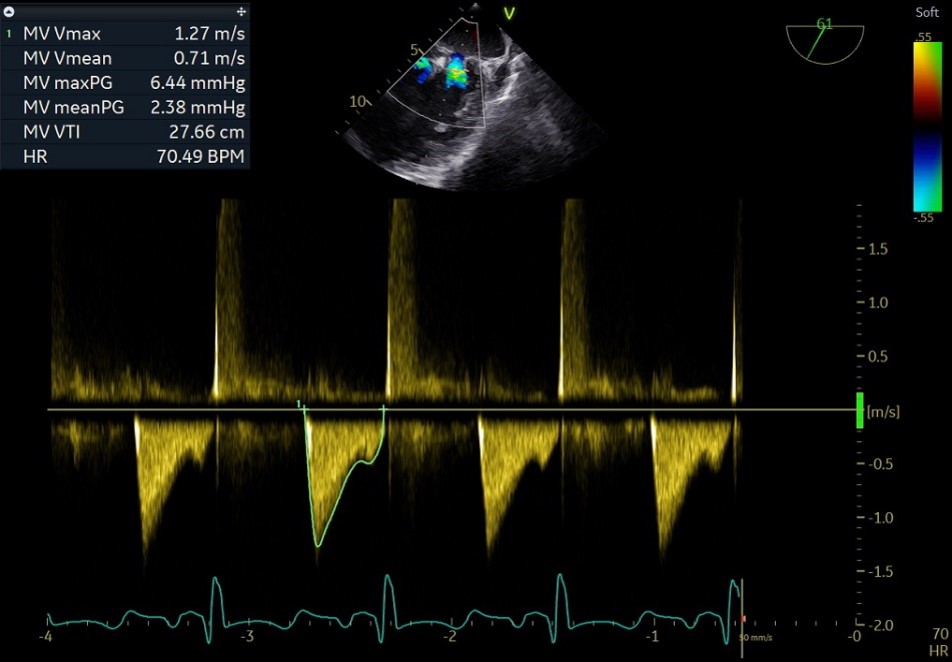

术后平均跨瓣压差

释放后

外侧2偏1区可见后叶栓系,下方空间乳头肌腱索杂多,后叶长度也一般,跨瓣压差3mmHg,第三枚夹子选择了NT,打算靠近第一枚夹子2偏1区夹持,置入NT后,在1区上方做轨迹测试,充分释放张力,调整夹子的夹臂方向位于1点-7点的方向,回拉系统,使第三枚夹子靠近第一枚夹子,关小夹子进入到心室侧,由于第一枚夹子起到了稳定瓣叶的作用,第三枚夹子捕捞夹持相对顺利,一次精准捕获前叶和后叶,再次完整评估二尖瓣NT的方向、组织桥稳定性、瓣叶受限程度及反流减小程度。反流改善到1+-2+,平均跨瓣压差3.85mmHg,左房压明显下降,肺静脉逆流明显改善,手术完美结束。